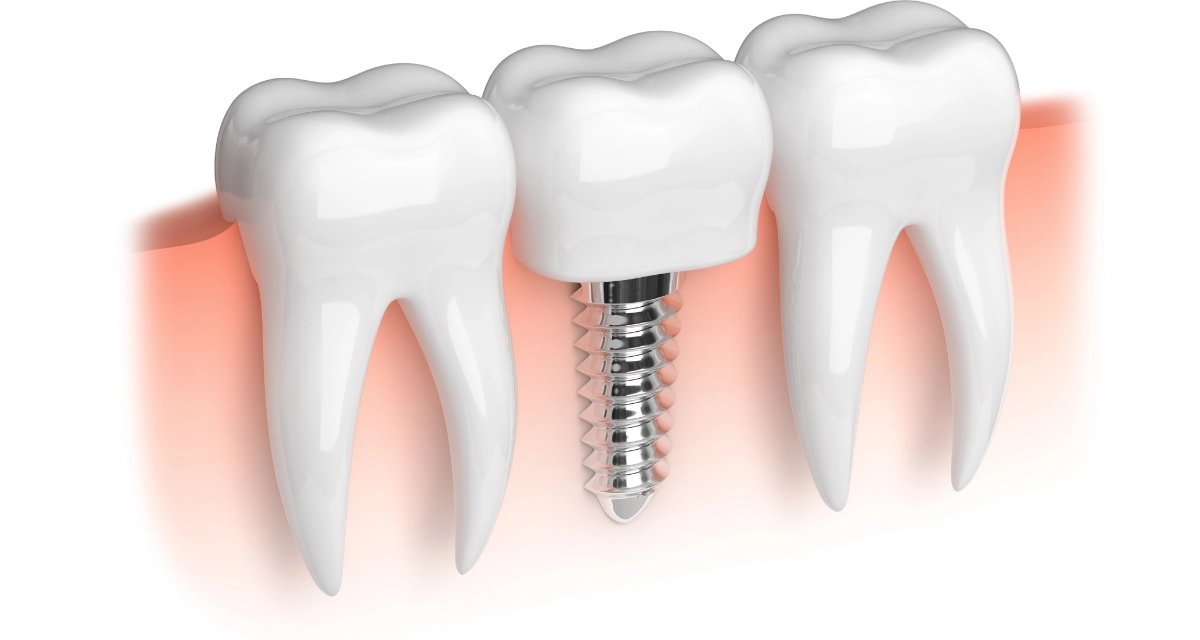

Dental implants are a permanent solution to missing teeth. Unlike dentures, which can be removed, dental implants are surgically placed into your jawbone and fuse with the bone.

Dental implants can improve your overall oral health. When you have missing teeth, it can create gaps in your smile that can make it difficult to eat, speak, and clean your teeth properly.

Dental implants can help to fill in these gaps and restore your smile, as well as improve your chewing and speaking ability.